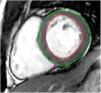

Tissue-tracking analysisTT analysis was performed using cvi42 software. For LV SAX sequences, the endocardial border was manually traced in ventricular end-diastole and the epicardial border was automatically detected and manually adjusted if deemed inadequate (Figure 2). Three levels were assessed: the atrioventricular ring (basal), the mid-ventricle where the papillary muscles were best visualized (mid), and the LV apex. The same technique was applied to 4-, 2- and 3-chamber sequences.